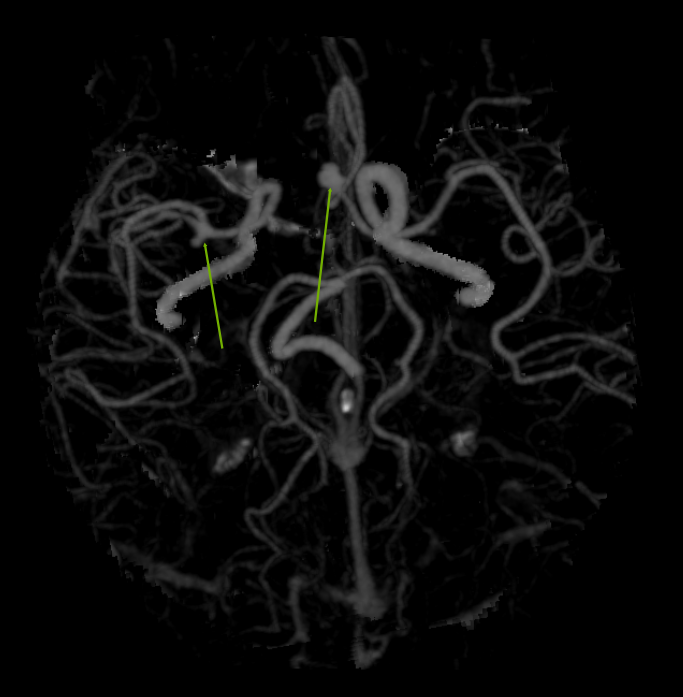

前交通动脉瘤没有理想的夹子,又想保护粘在动脉瘤上的一根静脉,采用头端可调持夹钳,左手把夹子送到位稳住,右手用剥离子调整夹子角度。